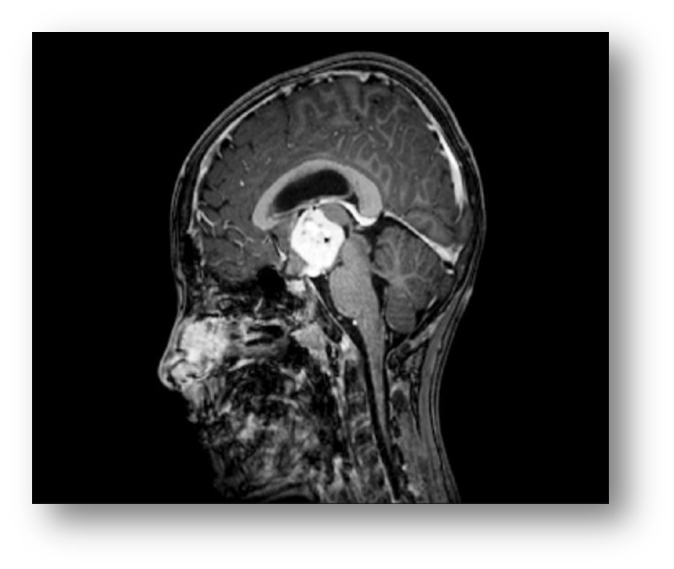

1. Рис.1 Глиома | |